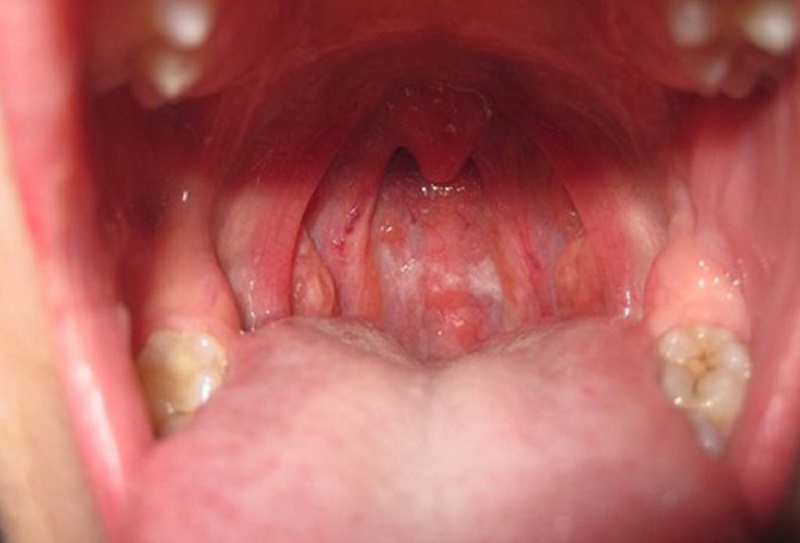

- Viêm nhiễm ở vùng đầu cổ: Các bệnh lý viêm nhiễm như sâu răng, viêm họng, viêm xoang, viêm tuyến nước bọt, viêm amidan, viêm lợi, viêm da đầu, nhiệt miệng,... thường khiến hạch cổ nổi lên và sưng đau.